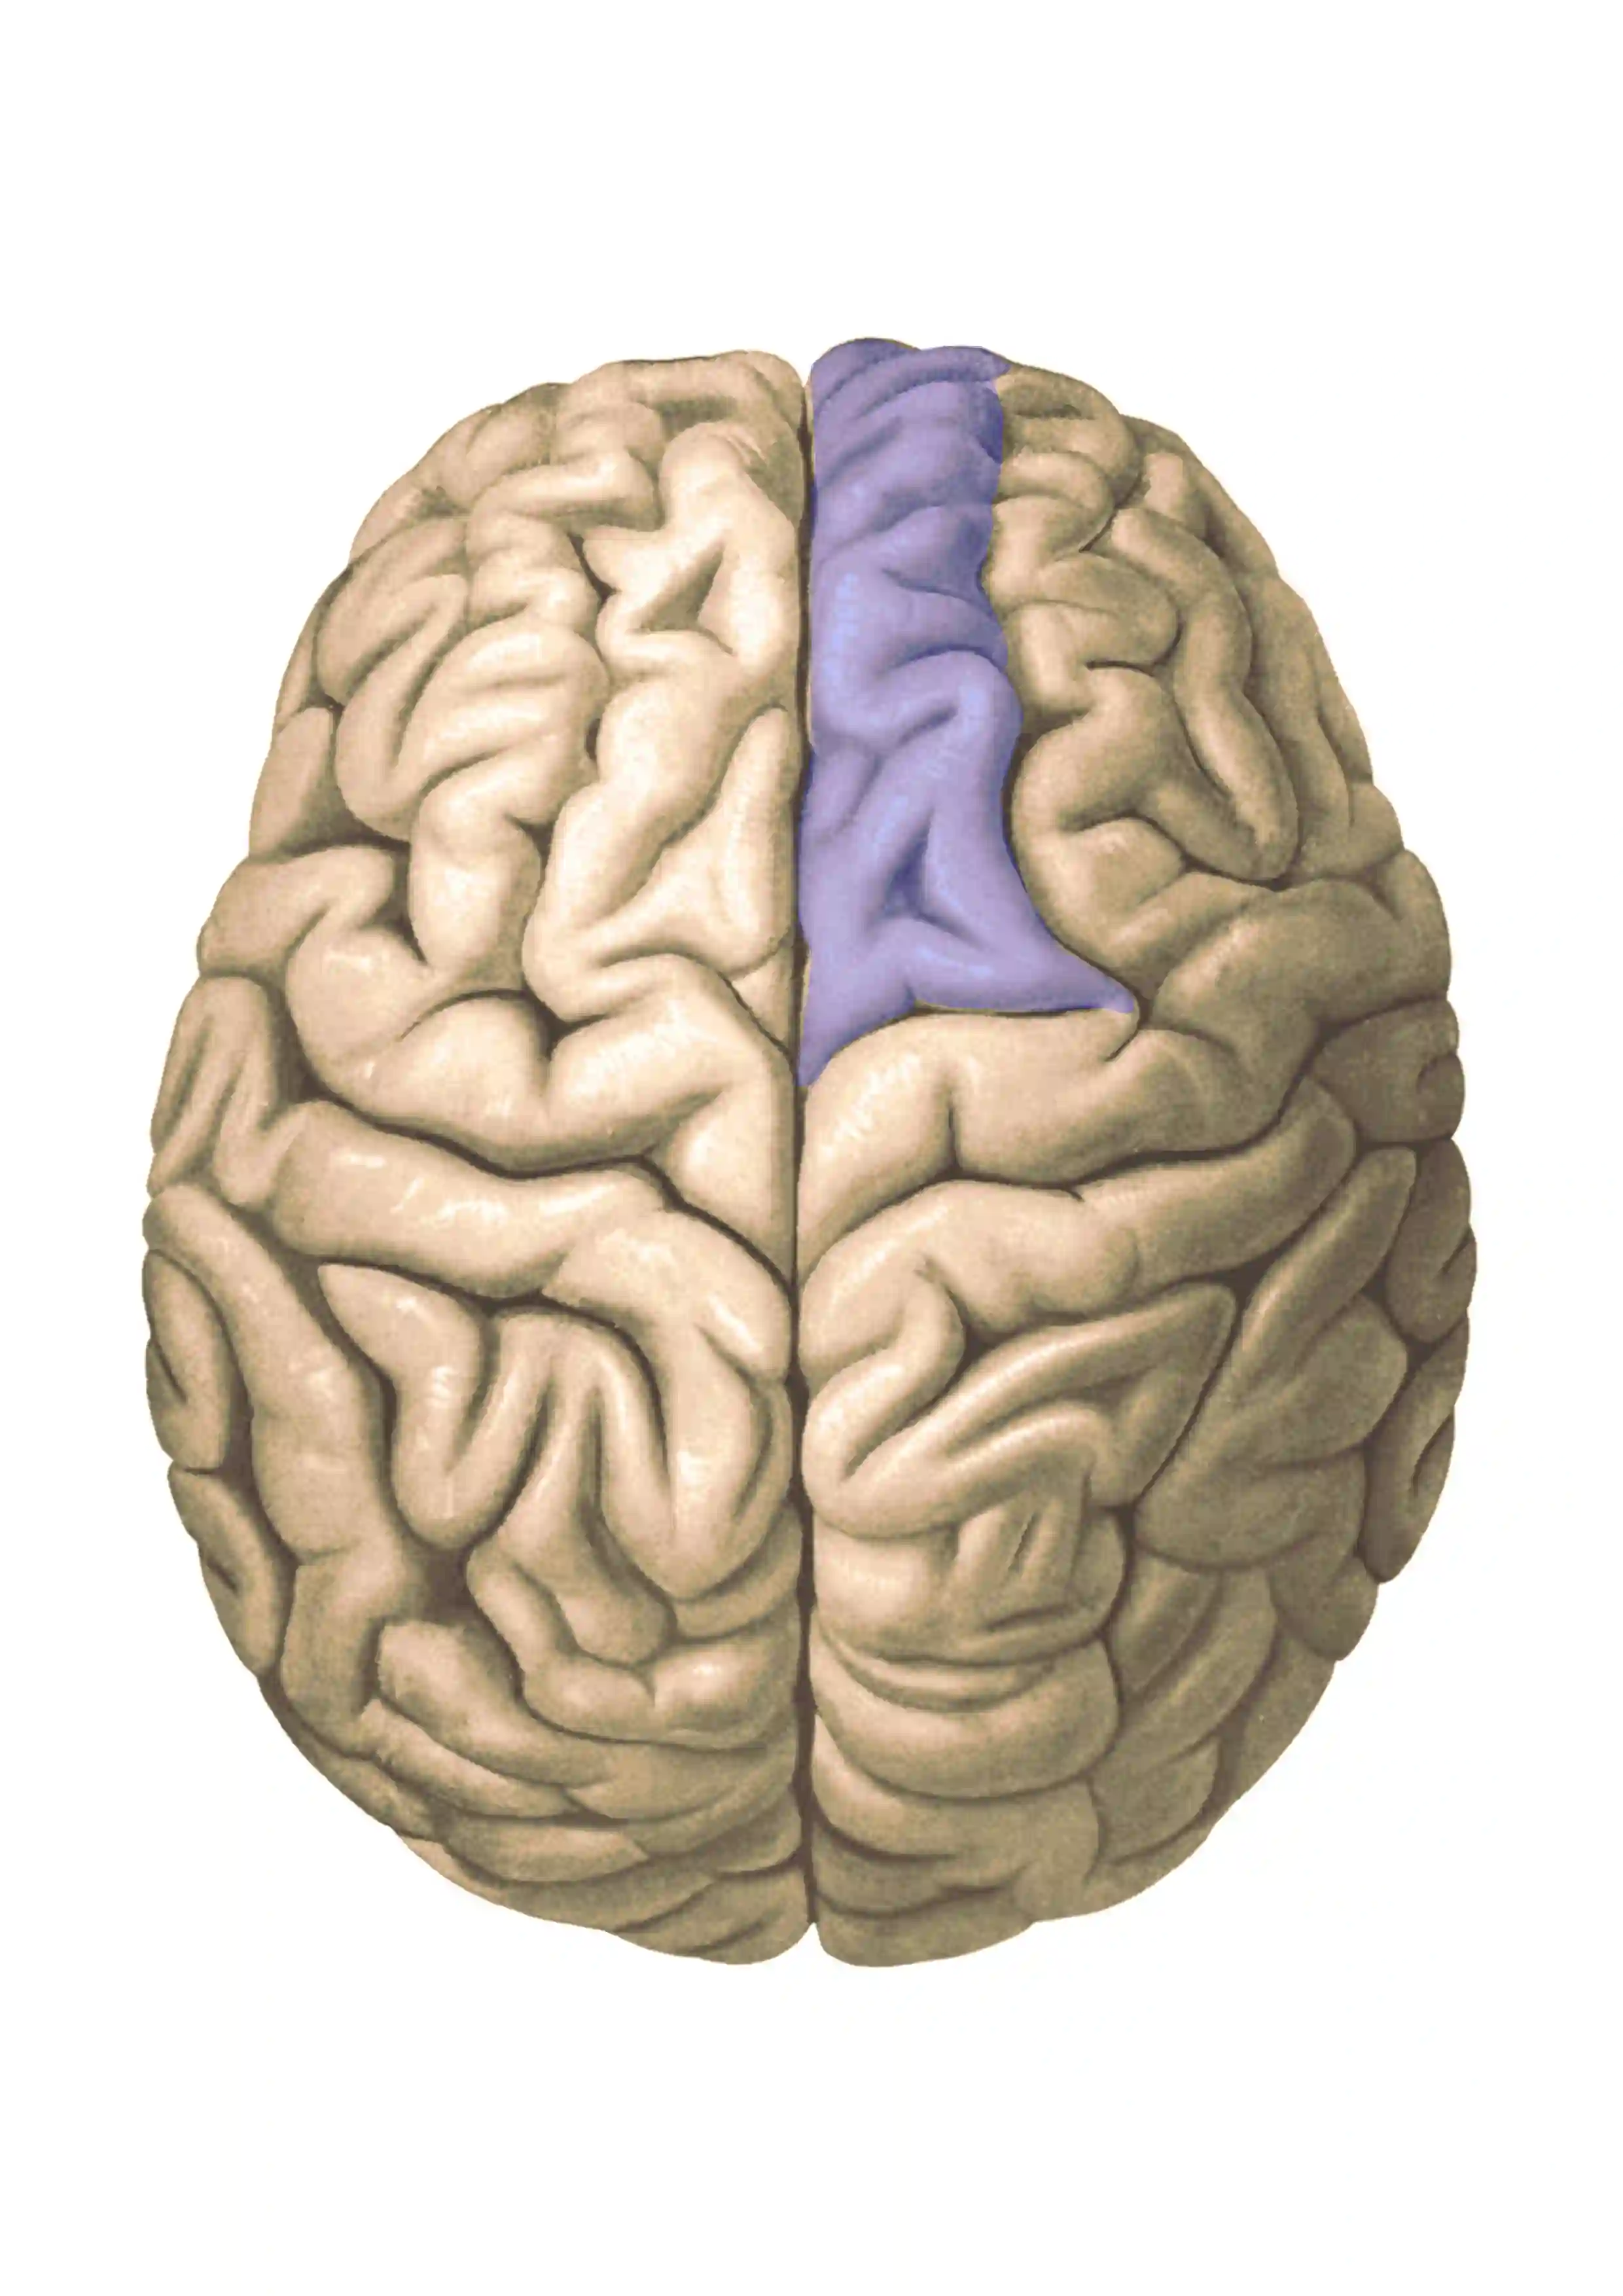

Gyrus frontalis superior

Anatomische Abbildung der Gyri und Sulci des Gehirns mit einseitig eingefärbtem Gyrus frontalis superior (blau gefärbt). Abbildung adaptiert ausAtlas and Textbook of Human Anatomy, 1909, Vol. 3, Figure 628, by Johannes Sobotta and J. Playfair McMurrich